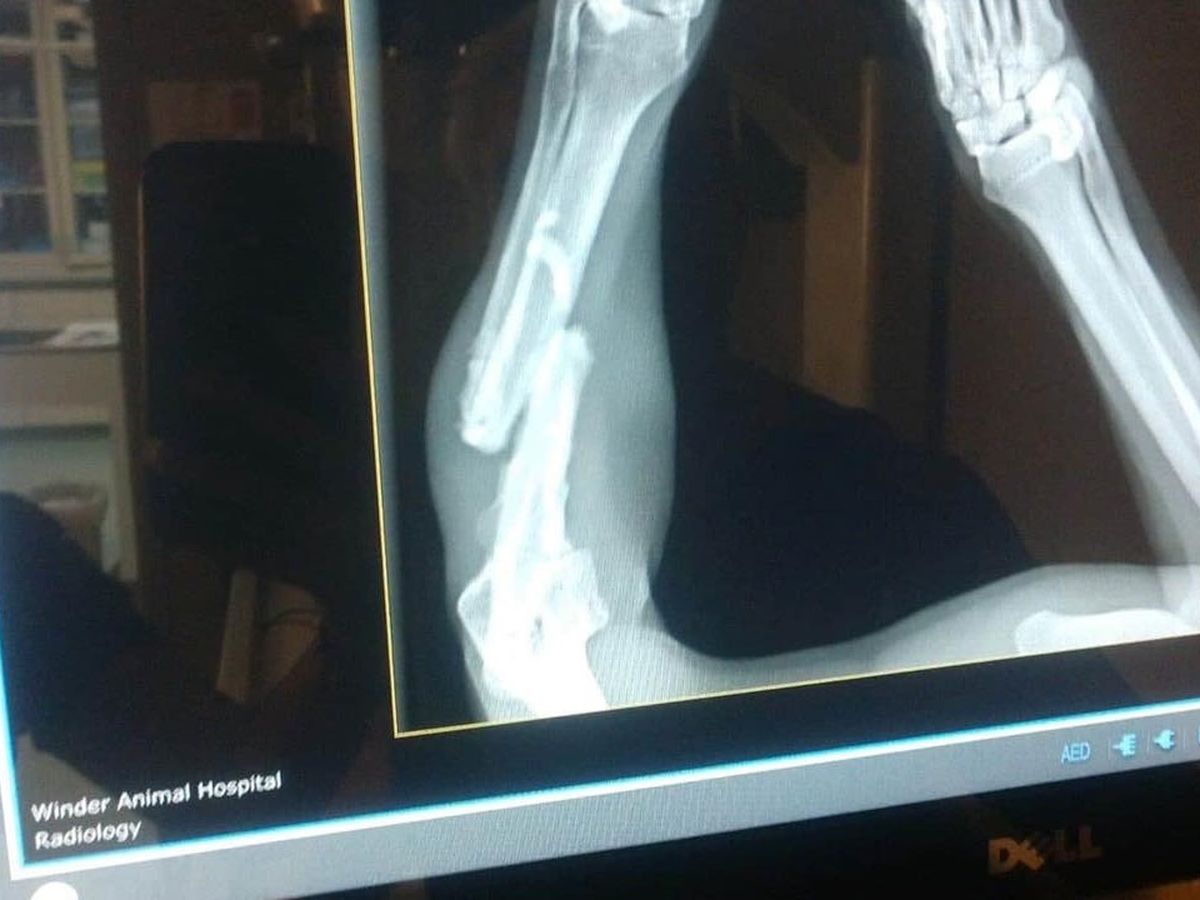

Hi, everyone! Trooper here. I recently landed at Barrow County Animal Shelter with a bad leg. They sent me to the vet for an x-ray and OUCH! You can see what's going on.